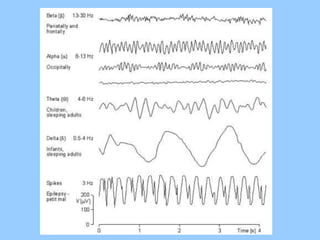

3. International standards for EEG electrode placement and recording parameters are reviewed. Characteristics of different EEG waves, amplitudes, and patterns are described.